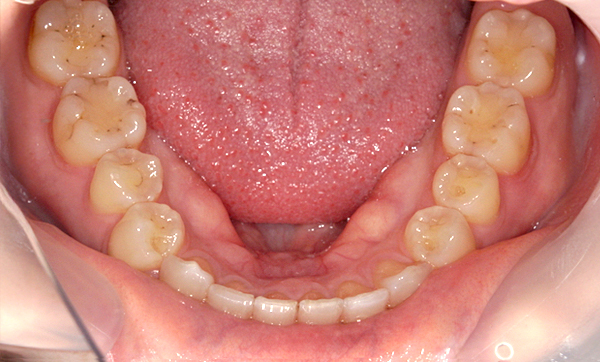

| 治療前 | 治療後 |

|---|---|

|